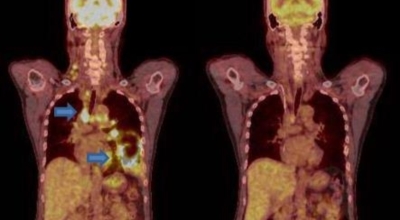

폐암 검사는 X-ray를 통해서 검사하는데 , 크기가 작거나 구석에 위치한 경우 확인이 어려운 경우도 있답니다. 그리고 조직 검사를 통해서 정확한 진단을 하게 되어요. 폐암이 발견되면 종양의 크기나 전이 여부 , 위치에 따라서 수술 여부를 결정하게 되어요.

수술 치료

악성 종양이 있는 폐의 일부를 절제하는 방법입니다. 초기에는 내시경 기구를 활용하여 수술이 가능하기도 합니다.

항암 치료

항암제를 이용한 치료 방법입니다. 폐암 4기 같은 경우에는 항암 화학요법이 유일한 치료방법이기도 합니다. 폐암에 대해서 알아봤는데요.